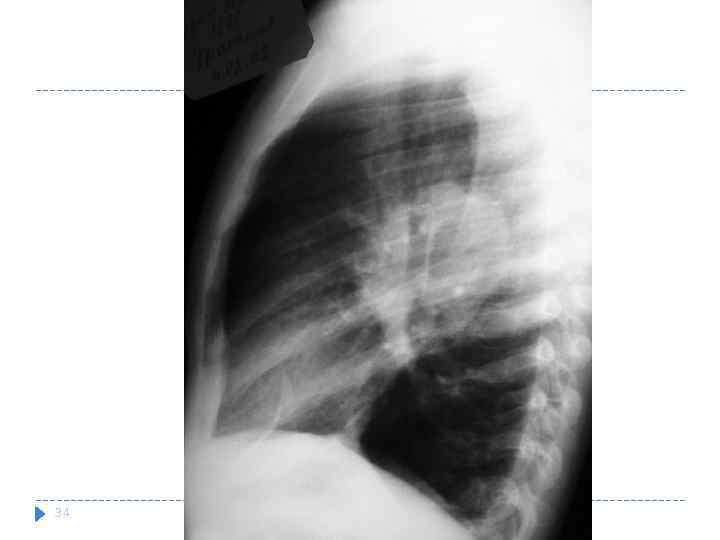

34

34

Левосторонний туморозный бронхоаденит. Массивное увеличение бронхо-пульмональных лимфатических узлов. а — обзорная рентгенограмма; б — томограмма.

Левосторонний туморозный бронхоаденит. Массивное увеличение бронхо-пульмональных лимфатических узлов. а — обзорная рентгенограмма; б — томограмма.